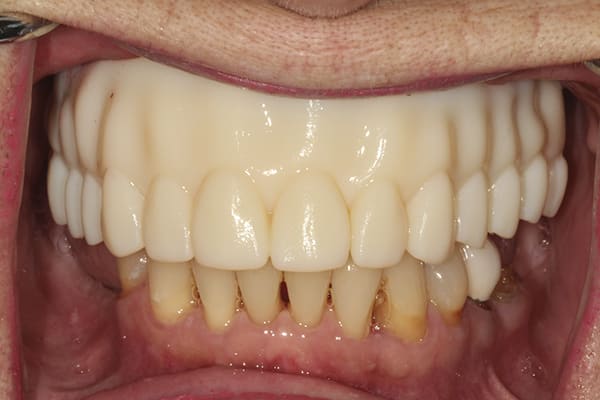

A 72-year-old woman presented with pre-existing dental implants in the approximate positions of Nos. 3, 5, 8, 11, and 14. Because of the patient's age and history of osteoporosis, the surgeon who performed the implant placement had had difficulty locating adequate bone to support the implants. Although the implants were osseointegrated with no clinical signs of mobility, a moderate amount of bone loss around each one was evident. The patient was initially treatment-planned for a crown-and-bridge FP3-style fixed restoration. However, after extensive discussion regarding her concerns, which included a desire for a more esthetically pleasing smile, she opted for a removable RP4-style LOCATOR® bar overdenture restoration (Zest Dental Solutions, zestdent.com), which she would be able to clean and maintain regularly and independently. A vinyl polysiloxane (VPS) impression was made of the implants and a prototype restoration designed. With the prototype used as a guide, a bar framework with four LOCATOR abutments was fabricated. Denture teeth were applied to the framework suprastructure, and the fit of the bar and the tooth arrangement were evaluated intraorally. Upon patient approval, the restoration was finalized and processed using conventional methods. The patient returned for prosthesis placement, and the LOCATOR bar was placed onto the implants. The prosthesis was then placed onto the bar ensuring its stability, and esthetics, phonetics, and occlusion were confirmed.

The RP4-style LOCATOR bar overdenture restoration used in this case provided the patient the esthetics she desired while giving her the ability to remove, clean, and maintain the prosthesis.